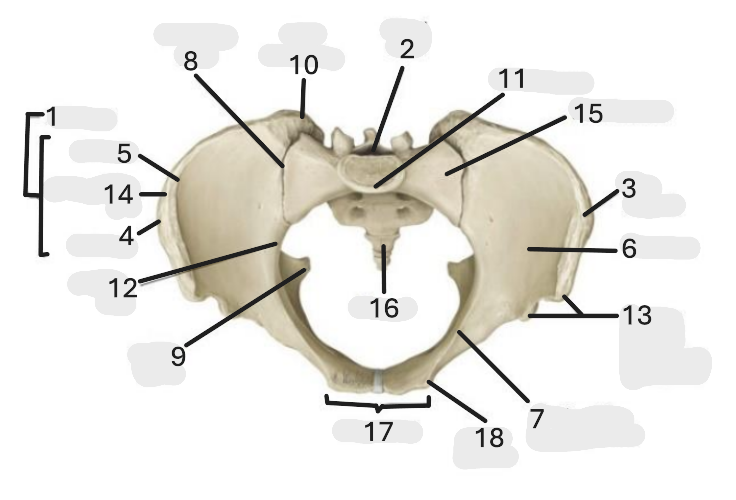

Where is the iliac crest

1

where is the sacral canal

2

Where is the iliac tubercle

3

Where is the outer lip

4

Where is the inner lip

5

Where is the iliac fossa

6

Where is the pectineal line (pecten pubis)

7

Where is the sacroiliac joint

8

Where is the ischial spine

9

Where is the iliac tuberosity

10

Where is the promontory

11

Where is the arcuate line

12

Where is the anterior superior and inferior iliac spine

13

Where is the intermediate line

14

Where is the ala of the sacrum

15

Where is the coccyx

16

Where is the pubic crest

17

Where is the pubic tubercle

18